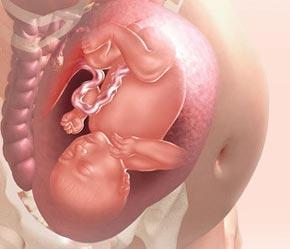

La evolución semanal del feto.

Hagamos un pequeño repaso por las semanas anteriores para ver en que estado se encuentra nuestro bebé en este momento, recordábamos que estas últimas semanas la función principal para el bebé es coger peso y estar totalmente preparado para el momento del parto, ya tiene consciencia e incluso sueña, aunque no sabemos muy bien con que puede soñar un niño que aun no ha visto nada, mi opinión personal es que los sueños irán en función de lo que ha estado escuchando el bebé en el corto periodo en el que ha desarrollado su sentido del oído, también veíamos que las fontanelas del bebé eran los únicos (huesos) que no se endurecían para permitir la salida del bebé en el canal del parto, pero veamos que ocurrirá en la semana 34 del embarazo.

- Las medidas son de poco más de 44 centímetros, de la semana pasada a esta prácticamente no ha crecido. Lo que si sigue haciendo es engordar, llegando a los 2,2 kilogramos de peso.

- Aunque las proporciones de la cabeza son mayores a las del resto del cuerpo la cabeza sigue creciendo (a un ritmo inferior que el resto para así igualarse las proporciones en un periodo de tiempo) Al igual que la cabeza también lo hace el cerebro y sus conexiones cerebrales se van organizando mejor para estar totalmente preparado en el momento del parto y empezar a acumular y organizar toda la información que va a recibir del mundo exterior.

- Aunque pasa la mayor parte del tiempo dormido, en los momentos que está despierto empieza a estar más atento intentando recopilar información que le será útil en un futuro.

- Cada día que pasa el espacio con el que cuenta el niño es menor, lo que sigue limitando sus movimientos, aunque es posible que si que lo notes con más fuerza, aunque siempre en los mismos sitios, también sigue colocándose en su postura favorita, boca-abajo con la cabeza en el cuello del útero, como preparado para salir al mundo.